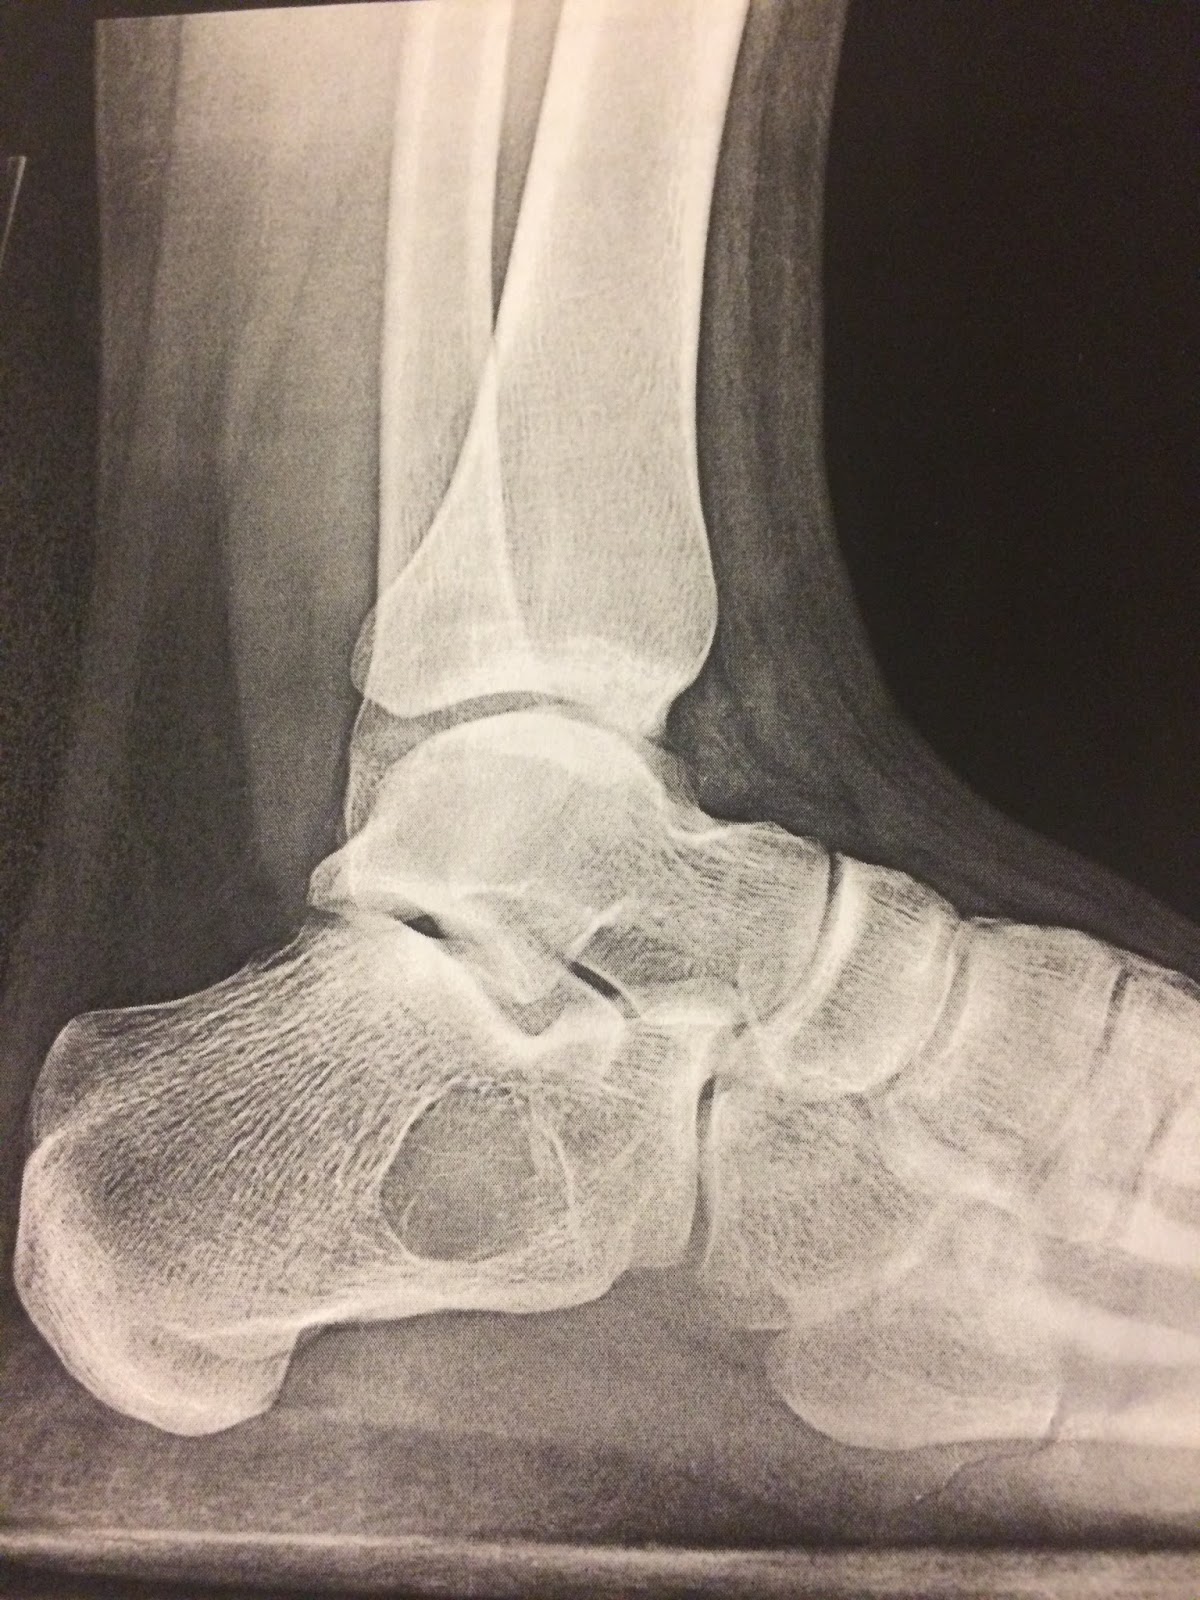

![]() |

| See the round/hollow spot? |

My youngest, Avery, had surgery to fix a large bone cyst inside her heel bone. OUCH. She’ll be in a cast for 6-8 weeks. The poor kid has been a champ. She’s starting to get antsy but we’re keeping her busy with school work, books, and activities. Hooray for the Feminist Activity Book!